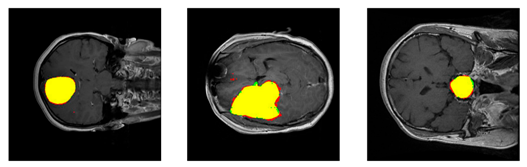

In medical software development, requirements analysis should first clearly define the purpose of the system. In the case of medical image segmentation, this means specifying which diagnostic problem the system is intended to solve. Examples include automatic segmentation of tumors in MRI scans (as shown in Figure 1) or delineation of anatomical structures in CT images.

Figure 1. Examples of segmentation results for meningioma, glioma, and pituitary tumors, respectively. Figure sourced from [1].